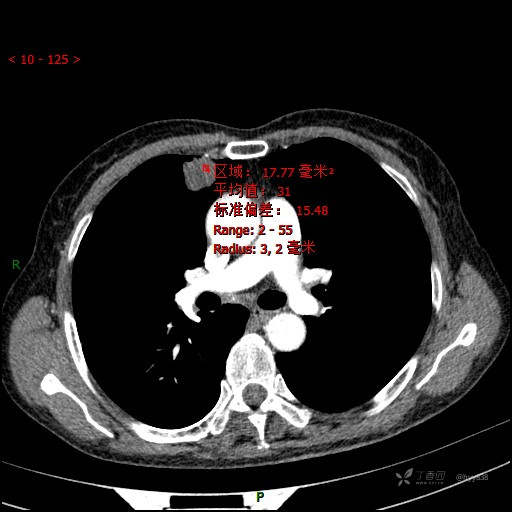

胸部CT平扫

CT值